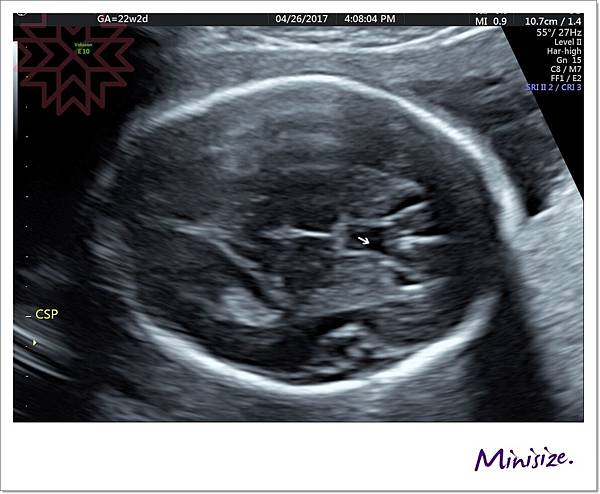

腦

箭頭處為透明中膈要明顯

左右腦也要對稱